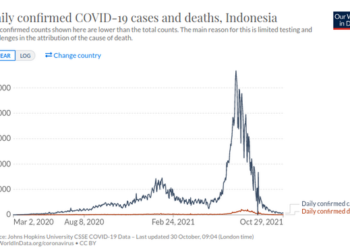

Tampaknya seluruh dunia sudah menjadi gila setelah “varian” Covid19 baru yang disebut Omicron muncul. Propaganda, disinformasi dan ketakutan yang menyebar dari Pemerintah dan Media telah mencapai tingkat absurditas baru. Jadi...